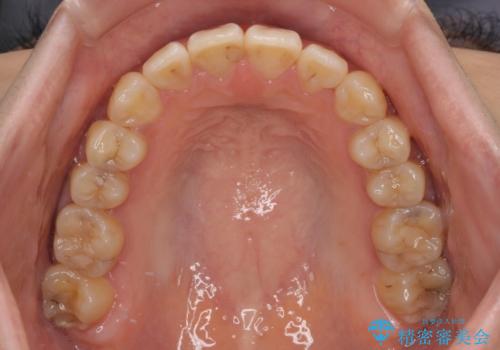

- 上下前歯の非接触と叢生を気にして来院された患者様です。

開咬の改善はインビザラインの最も得意とするところであるため、インビザラインを用いて矯正治療を行うこととしました。

治療開始直後に上顎前歯に激しい痛みが発現し、矯正治療を休んだり、マウスピースの装着時間を短くしたりと工夫をしましたが、残念ながら治療途中で失活していることが分かりました。

矯正治療の途中で前歯の根管治療とオールセラミッククラウンによる補綴治療を行い、その後インビザライン1セットを用いて細かい部分を仕上げました。